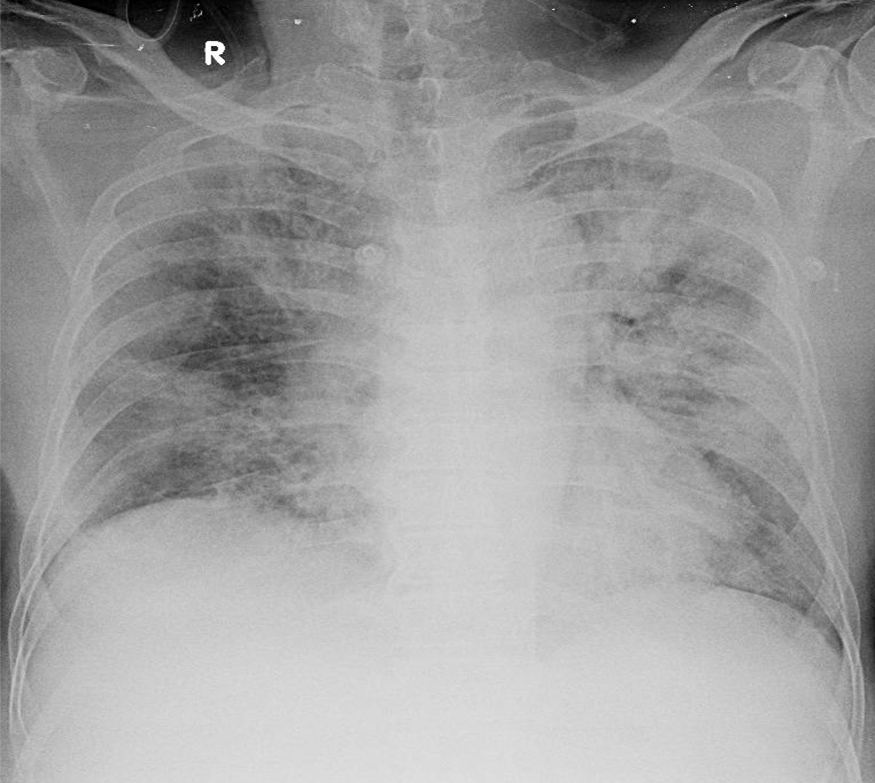

1-Tổn thương phế nang lan tỏa hai phổi => Viêm phổi